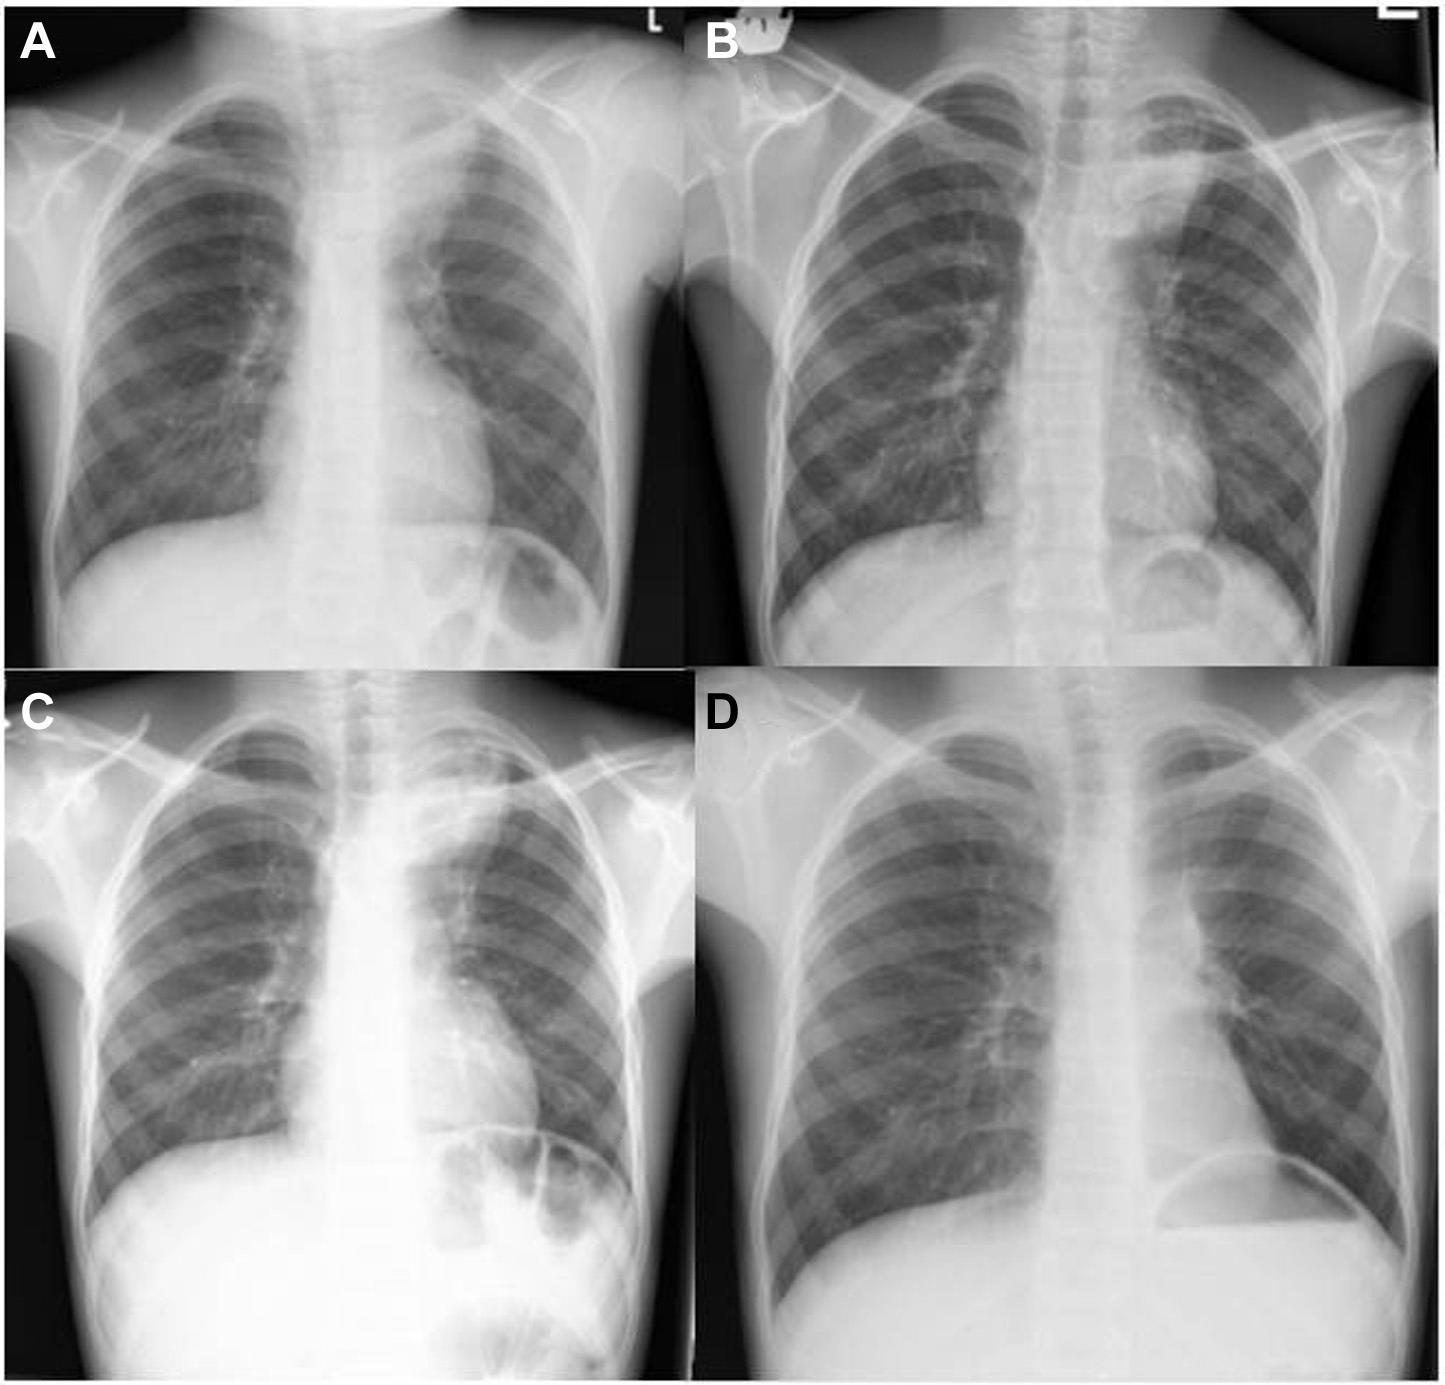

图1 胸片

A 左上叶实变(2017.07) B 18个月后左上叶实变(2019.01)

C 阿苯达唑

治疗后左上叶实变(2019.06) D 左上叶切除术后;右叶无实变,轻度的过度充气。

正常,仅有几张胸片显示左上肺叶有肺泡浸润(图1 A,B),在接受了7天的阿莫西林

后虽有所好转,但效果一般。

左上叶切除术后,患者继续接受了6个月的阿苯达唑治疗,胸痛症状完全消失,随访胸片显示其他肺叶无浸润和肺不张

(图1 D)